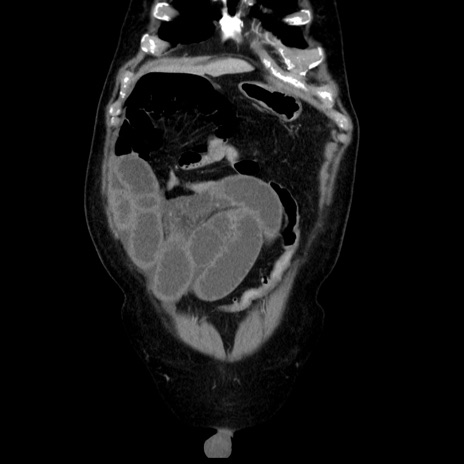

症例30(冠状断像)

【症例】80歳代男性

【主訴】臍周囲痛

【現病歴】約6時間前から臍下部痛が出現。次第に腹部膨隆・背部痛も生じてきたため来院。背部痛の場所は変化しない。

【身体所見】意識清明、BT 36.3℃、BP  131/87mmHg、P 87bpm、SpO2 100%(RA)、臍周囲自発痛・圧痛あり、反跳痛なし、自発痛部位に一致して板状硬あり、腹部膨隆、腸雑音減弱、CVA tenderness両側陰性。